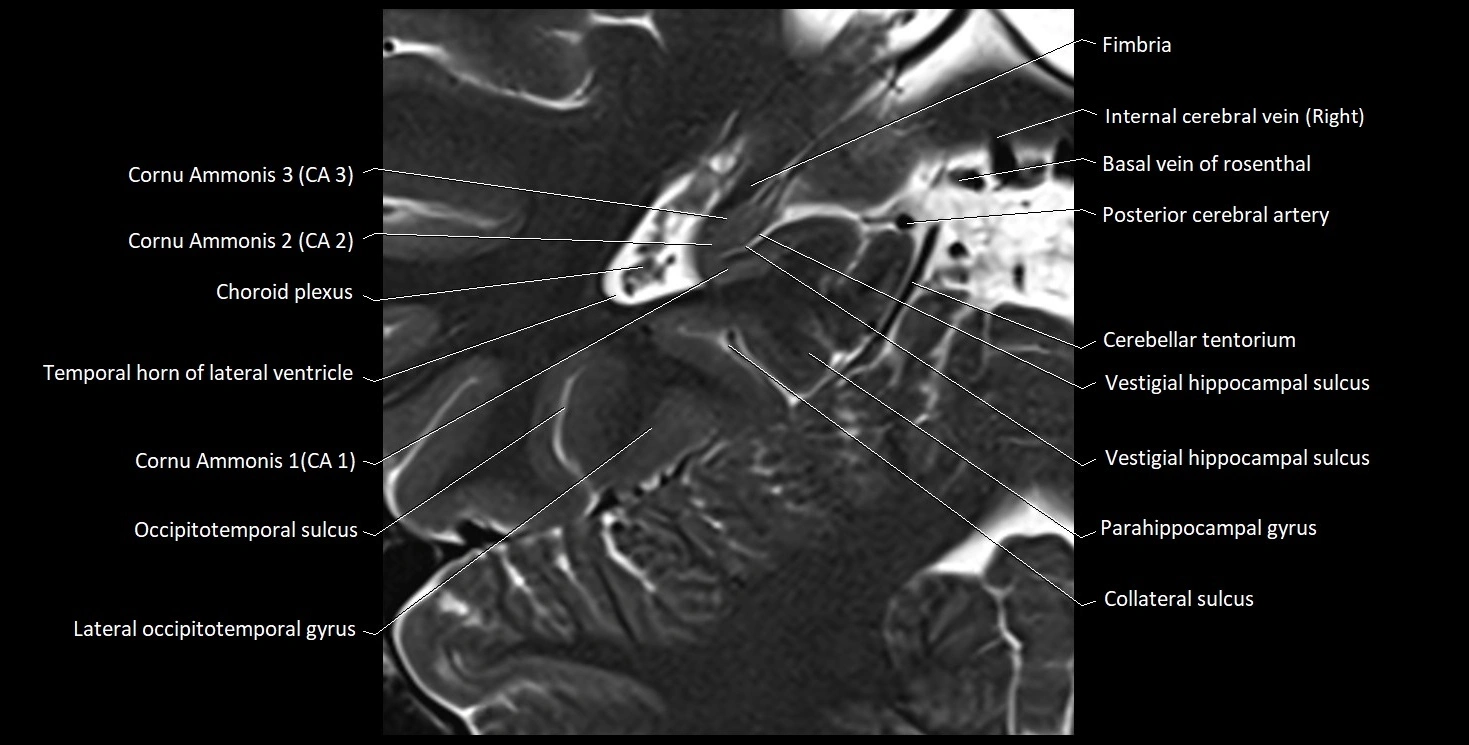

MRI images

image